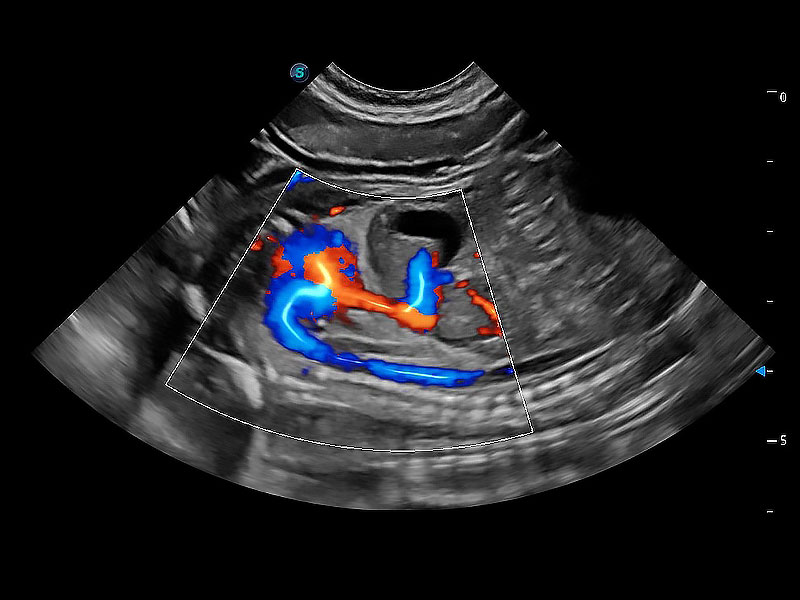

(犬)胎儿主动脉弓立体血流

(犬)胎儿四腔心

得心应手 心脏解决方案

ProPet 80 配备了丰富的心脏探头群、先进的成像技术和专业的心脏测量工具,可帮助动物医生为不同体型和生理结构的动物提供心脏和心肌功能的全面评估。

• TDI 组织多普勒成像

实时用颜色表示心肌组织运动,观察和定量组织的运动情況,对快速检测与评估心肌的灌注和活性、电传导及心肌收缩和舒张功能等均能提供重要的诊断信息。